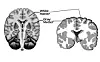

MR-bildet til venstre viser en frisk hjerne, mens hjernen til høyre tilhører en person med Alzeheimers sykdom. Foto: Timothy Rittman / University of Cambridge/AFP/NTB

MR-bildet til venstre viser en frisk hjerne, mens hjernen til høyre tilhører en person med Alzeheimers sykdom.

Det er usikkert nøyaktig hva det er som forårsaker tap av grå substans, men de største tapene ses hos folk som også opplevde at luktesansen ble påvirket i større grad og over lengre tid. Forskerne vegrer seg fra å slå full alarm, men mener at det er et tegn på at man vil kunne se en fremtidig kobling mellom covid-19 og demenssykdom, inkludert Alzheimer.